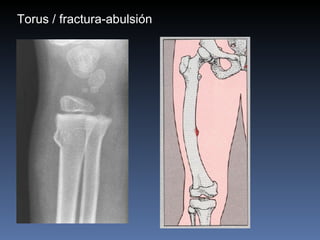

Fracturas en Niños Arqueamiento plastico - fractura sin rotura de la cortical Torus – cortical abulsionada Tallo verde – ruptura de la cortical en un lado del hueso Fractura de Salter-Harris - una fractura que involucra el disco de crecimiento

Torus / fractura-abulsión